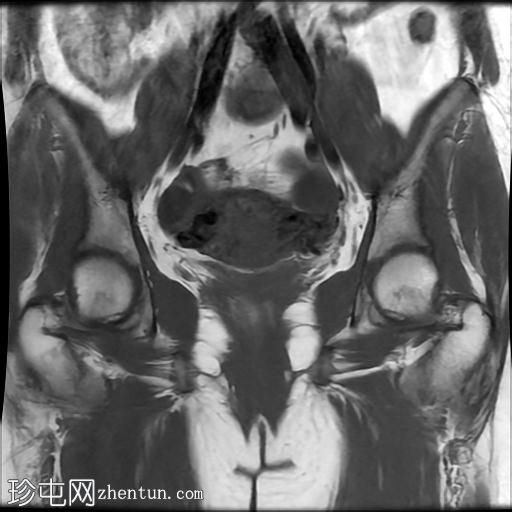

冠状位

T1加权像

盆腔MRI显示双侧子宫旁多条迂曲静脉,自子宫肌层延伸至盆腔。

此外,左侧附件可见两个充满液体的单纯性囊肿,大小分别约为31 mm和32 mm;右侧附件可见一个卵泡囊肿,大小约为19 mm。

影像学特征符合盆腔充血综合征的诊断,患者为35岁女性,有慢性盆腔疼痛和痛经病史。